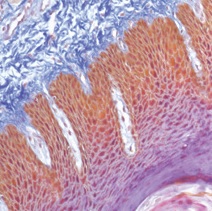

Gotowe zestawy do barwień specjalnych

MASSON TRICHROME KIT

• Zestaw siedmiu odczynników do barwienia mięśni i włókien kolagenowych z niebieskim barwieniem kontrastowym.

• Służy również do wizualizacji gamet, jąder, neurofibryli, komórek glejowych, keratyny, i włókien międzykomórkowych.

• op.-100 testów nr kat. MST-100T